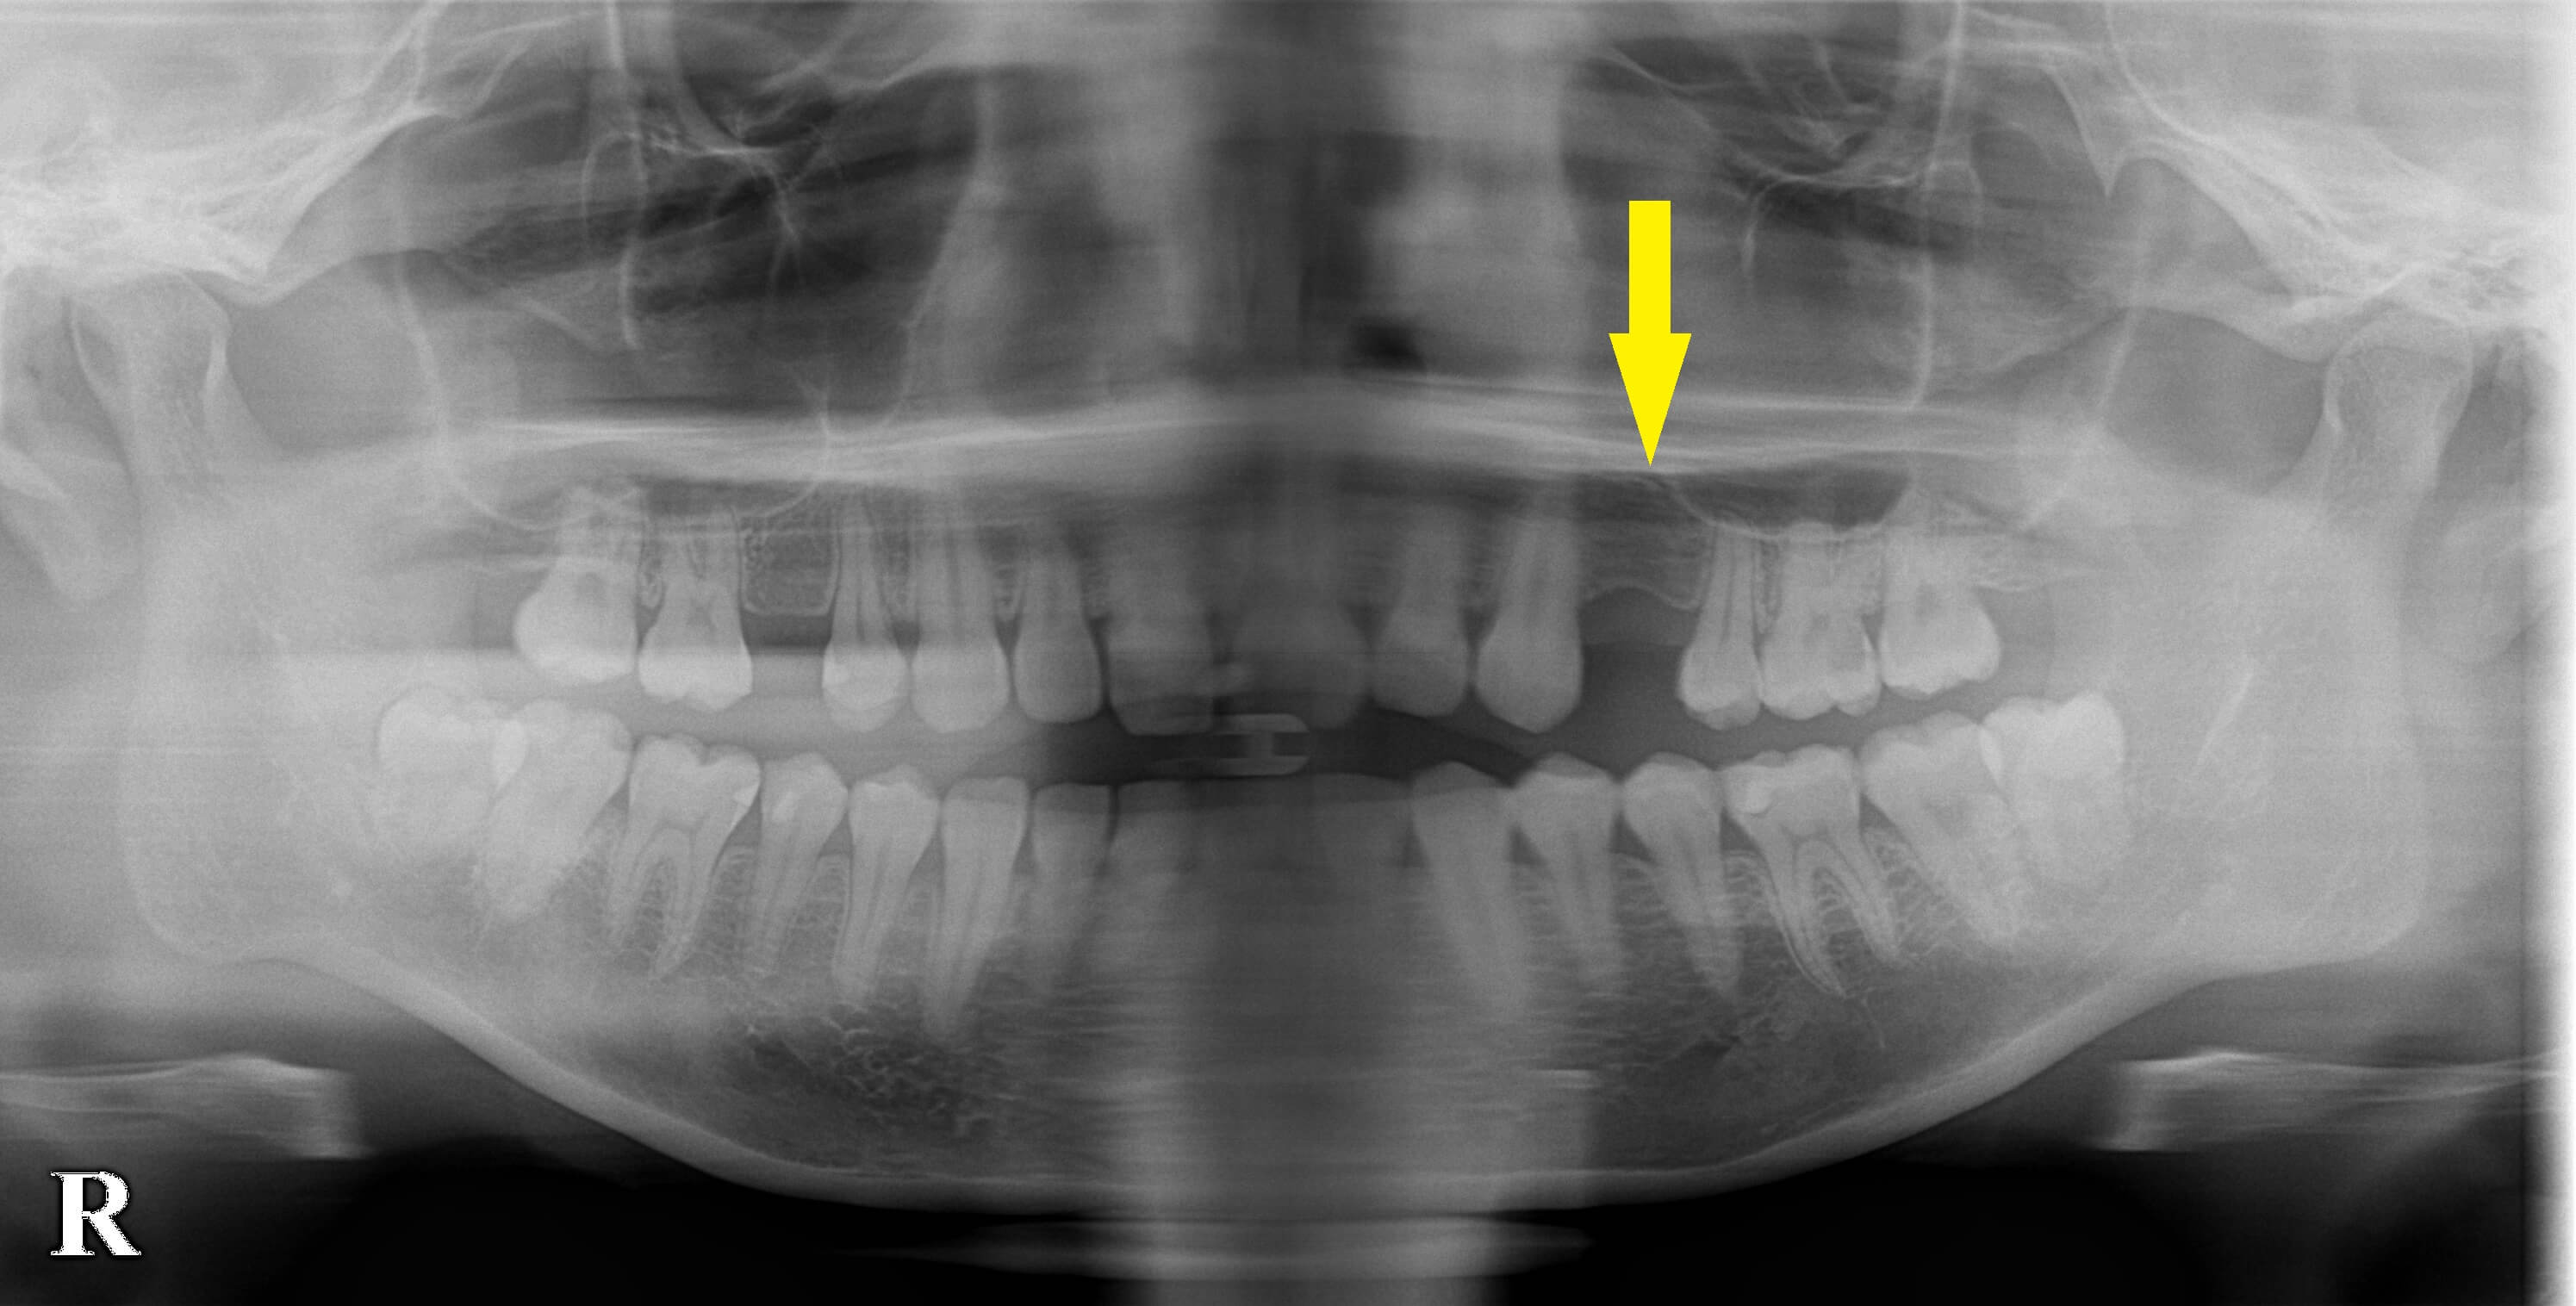

上顎両側の小臼歯にスペースが残っていて、ここにインプラントを埋入すればいいのですが、CTを撮影してみると左側は骨の高さも幅も不十分であることが分かりました。

下の写真、下段左の写真が、手術前の状態です。

インプラントを埋入するには、特に幅が狭く、困難な状態です。

下の写真、下段右の写真が手術後のCTです。

白く写る人工骨がインプラント上方と側方に確認できます。